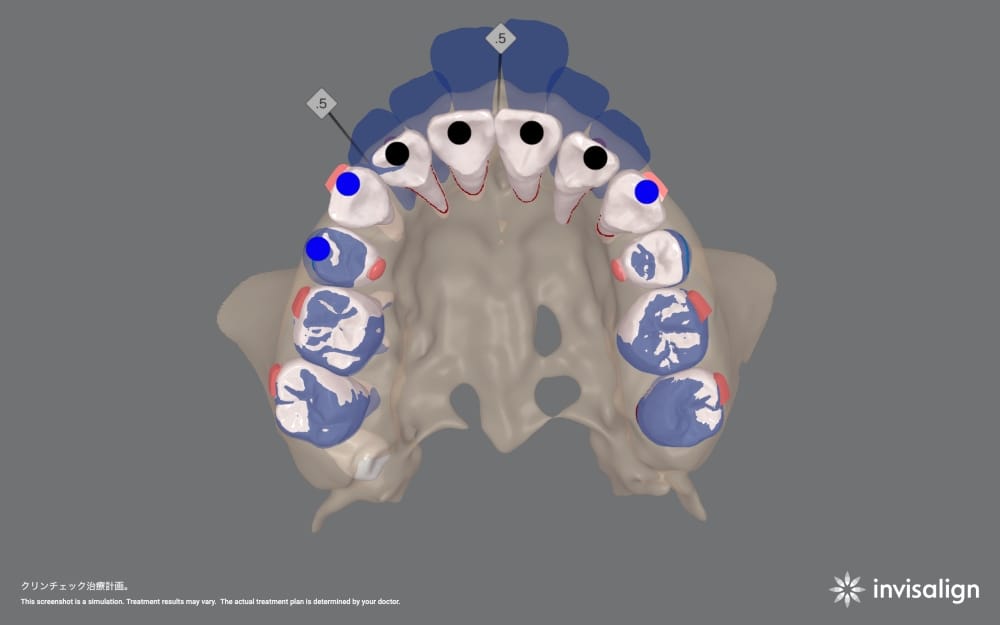

③ 歯列・噛み合わせデータの取得

口腔内スキャナーで歯型データを取得し、スペースの有無や前歯をどの程度後退させられるかをシミュレーションします。

単に“下げたい”という希望だけでなく、実際に動かせる範囲を具体的に検討します。

当院では、3Dシミュレーションを用いて「矯正単独でここまで変わる」というイメージを事前に共有します。そのうえで、治療を進めるかどうかを患者様ご自身に決めていただきます。

こうしたギャップを防ぐため、当院では治療開始前に3Dシミュレーションを行い、歯並びだけでなく口元の変化イメージまで確認していただきます。

具体的には、

- 前歯が何ミリ後退するのか

- 横顔の唇の位置がどの程度変化するのか

- Eラインとの関係はどう変わるのか

を視覚的に確認します。

当院では、精密検査後のカウンセリング時に

- 口元と横顔の分析

- セファロによる骨格診断

- 3Dシミュレーションによる仕上がり予測

を行い、「矯正だけでここまで変わる」という具体的なイメージを共有します。

before

実際の治療計画

治療前に想定した治療前後の横顔のイメージ